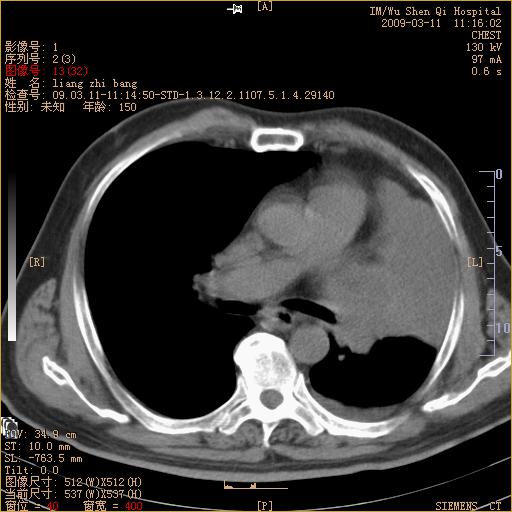

标题: CT18604:男,60岁,咳嗽一月余 [打印本页]

标题: CT18604:男,60岁,咳嗽一月余

1)考虑左肺上叶中央型肺癌并左肺上叶肺不张;建议必要时行纤支镜检查进一步明确诊断。2)左侧胸腔积液。

肺门肿块、支气管开口闭塞伴肺不张及胸水!典型的中心型肺癌变现!

1、左肺上叶中央型肺癌并上叶阻塞性肺不张。

2、左侧胸腔少量积液,右侧胸膜轻度增厚。

左肺们肿块并左肺上叶不张。考虑左肺中心性肺癌并左肺上叶不张及左侧胸腔积液